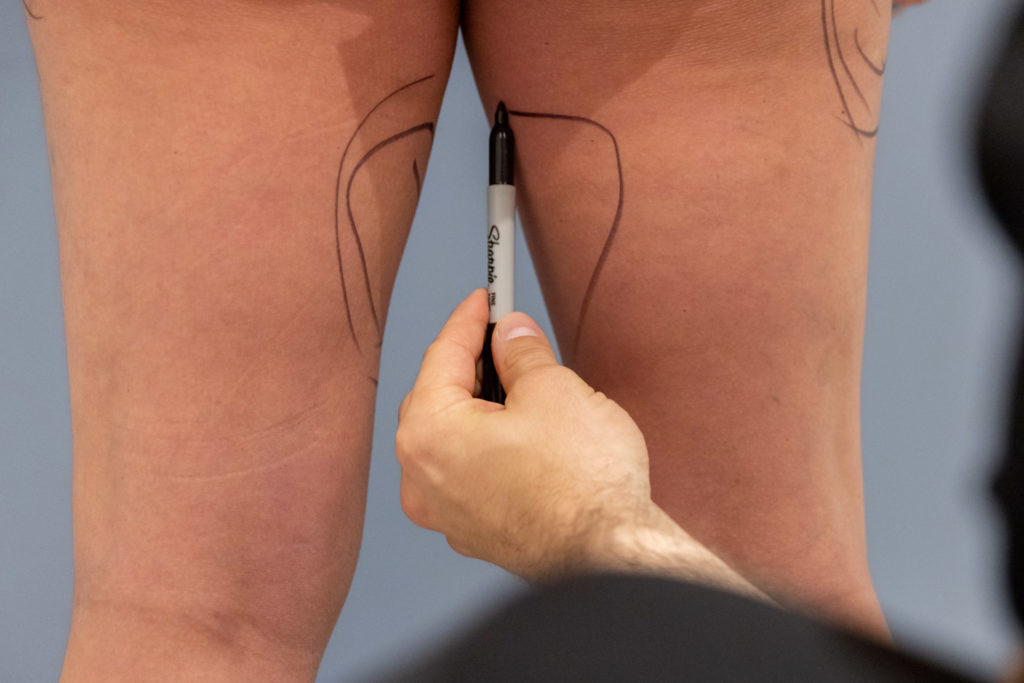

Body Sculpting

- Non-Surgical BBL